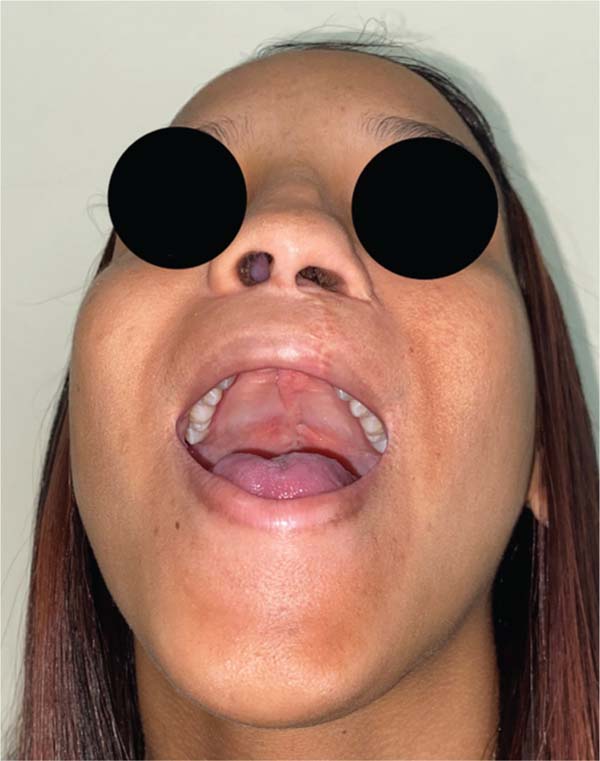

Further analysis revealed that one of these patients had a behavioral disorder with repetitive hand-to-mouth movements, as reported by the mother. In the second case, preoperative photographs revealed a velopalatine fossa and inadequate dissection by the surgeon, which contributed to fistula formation (►Figs. 4–11).

In the analysis of the cases of fistula in zone II, we identified a behavioral disorder in one subject, with a diagnosis of mild autism and maternal reports of repetitive hand-to-mouth movements, and, in another subject, a velopalatine fossa in preoperative photographs, indicating inadequate dissection as the cause of the condition. It is crucial to study ONF cases individually to understand the contributing factors and optimize the surgical approach to reduce its incidence.